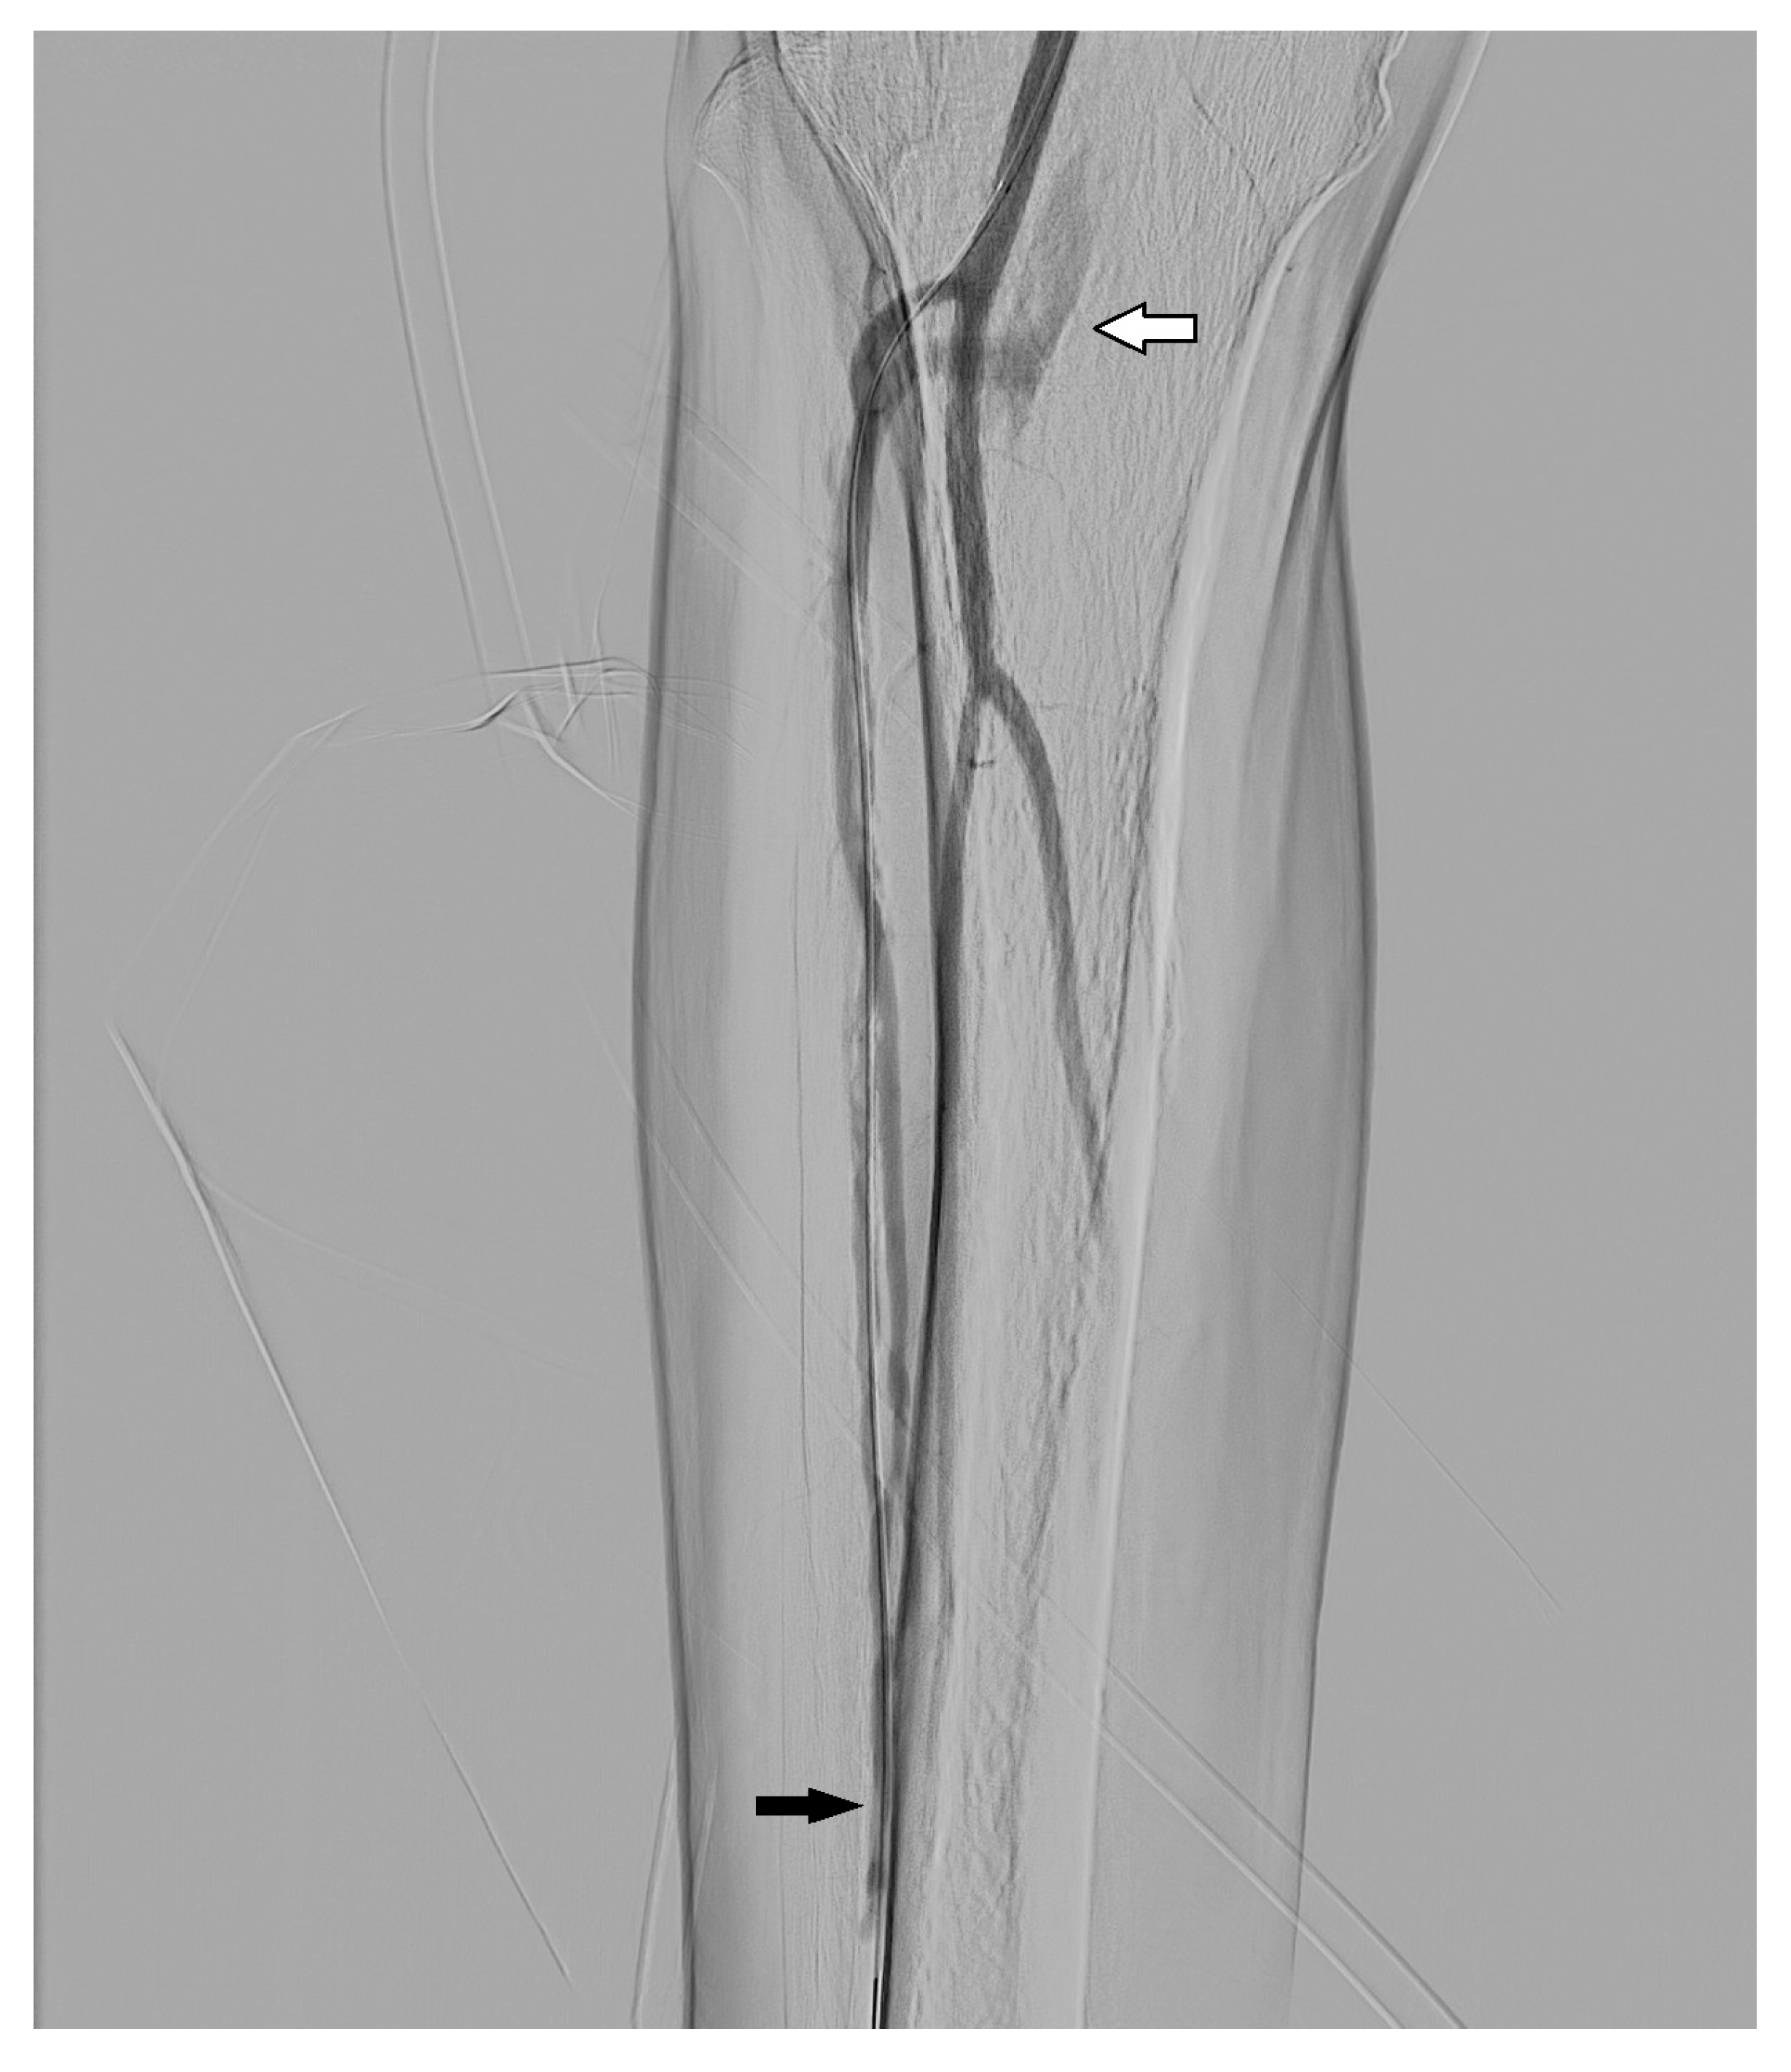

3.1. Stenosis and Occlusion

3.2. Dissection